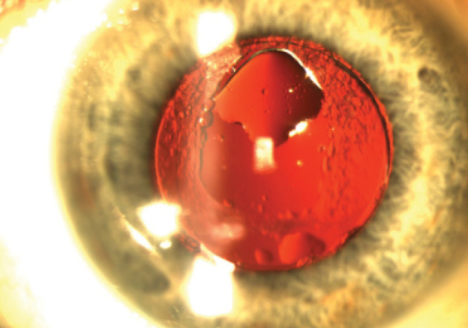

• Silicone Oil Deposits on an Accommodating IOL

CASE PRESENTATION Figure 1. Silicone oil adheres superiorly to the posterior surface of a well-positioned Crystalens in an eye with an open posterior capsule. A 54-year-old man presents with a…